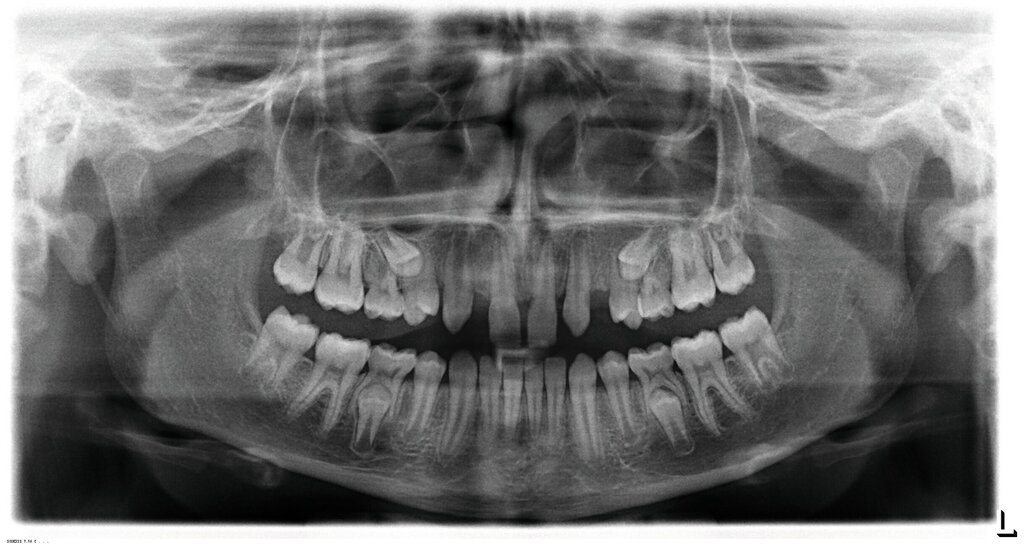

Bei dem gut zwölfjährigen Mädchen sind die seitlichen oberen Schneidezähne (Zähne 12 und 22) nicht angelegt. Zusätzlich zeigten sich verlagerte zweite obere Prämolaren.

Im vorliegenden Fall stand der Zahn 23 bereits im Mesialstand bei hoher Lachlinie und tendenziell konkavem Lippenprofil. Bezüglich Morphologie und Farbe waren die Zähne 13 und 23 nicht ausgeprägt eckzahntypisch. Es bestand kein Platzmangel im Gegenkiefer. Die Patientin war bei der Erstdiagnose 12,5 Jahre alt und im Wechselgebiss der zweiten Phase mit atypischer Durchbruchreihenfolge. Es bestand eine geringfügige Klasse II. Der Overjet war vergrößert bei vertikaler Wachstumstendenz, der Overbite war um circa einen Millimeter vergrößert aufgrund der geringfügigen Steilstellung der Oberkiefer-Front. Es bestand der Verdacht auf Nichtanlage der Weisheitszähne, 15 und 25 waren verlagert.